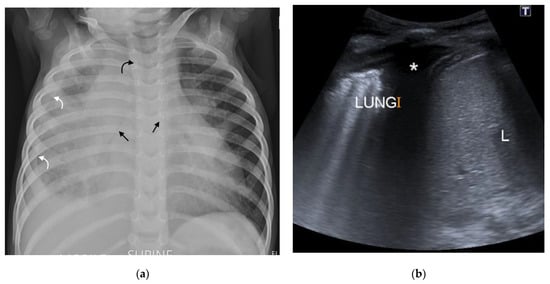

Figure 3. (a,b): Lymphadenopathy, air-space disease and airway compression on chest radiograph and CT. (a) Frontal AP chest radiograph in a 14-month-old boy with confirmed pulmonary TB demonstrating right hilar and paratracheal lymphadenopathy as lobulated masses projecting from the right of the cardio-mediastinal shadow (white arrows). There is also air-space disease in the right upper lobe, tracheal compression (black arrow) and left main bronchus compression (curved black arrow), resulting from presumed subcarinal and left hilar lymphadenopathy. (b) Axial post-contrast CT scan confirming the right paratracheal lymphadenopathy which has a low-density centre and fine rim enhancement (white arrow) and AP compression of the trachea (black arrow), which was not appreciated on the AP radiograph.

Figure 5. (ac): Lymphobronchial TB. Chest radiograph and CT in a 13-month-old boy with confirmed pulmonary TB: (a) The frontal AP chest radiograph is suggestive of bilateral hilar and paratracheal lymphadenopathy by the presence of bronchus intermedius and left main bronchus compressions resulting in bilateral (black arrows), mid and lower zone air-trapping. (b) Axial, post-contrast, soft-tissue-windowed CT scan at the level of the pulmonary trunk bifurcation demonstrates extensive subcarinal and hilar lymphadenopathy (black arrows) with marked bronchus intermedius attenuation (white arrow). (c) Coronal reconstruction of the post-contrast soft-tissue-windowed CT scan demonstrates paratracheal, sub-carinal and hilar lymphadenopathy (stars). There is attenuation of the bronchus intermedius and the left main bronchus (white arrows). There is also a suggestion of erosion of a right hilar lymph node into the lumen of the bronchus intermedius (black arrow).

CT is an excellent tool for assessing the airways and identifying multifocal, segmental areas of air-trapping, atelectasis, and consolidation [14,32]. Additionally, CT can help to determine the cause of tracheobronchial attenuation [1]. Extrinsic compression of a bronchus by an adjacent lymph node causes smooth luminal narrowing. Figure 5. This can create a ball valve phenomenon leading to distal air-trapping. Complete occlusion of the lumen can then result in atelectasis or consolidation and progress to necrosis and cavitation if left untreated [17]. Irregular bronchial lumen narrowing may indicate erosion of an adjacent node into the lumen [1,14].